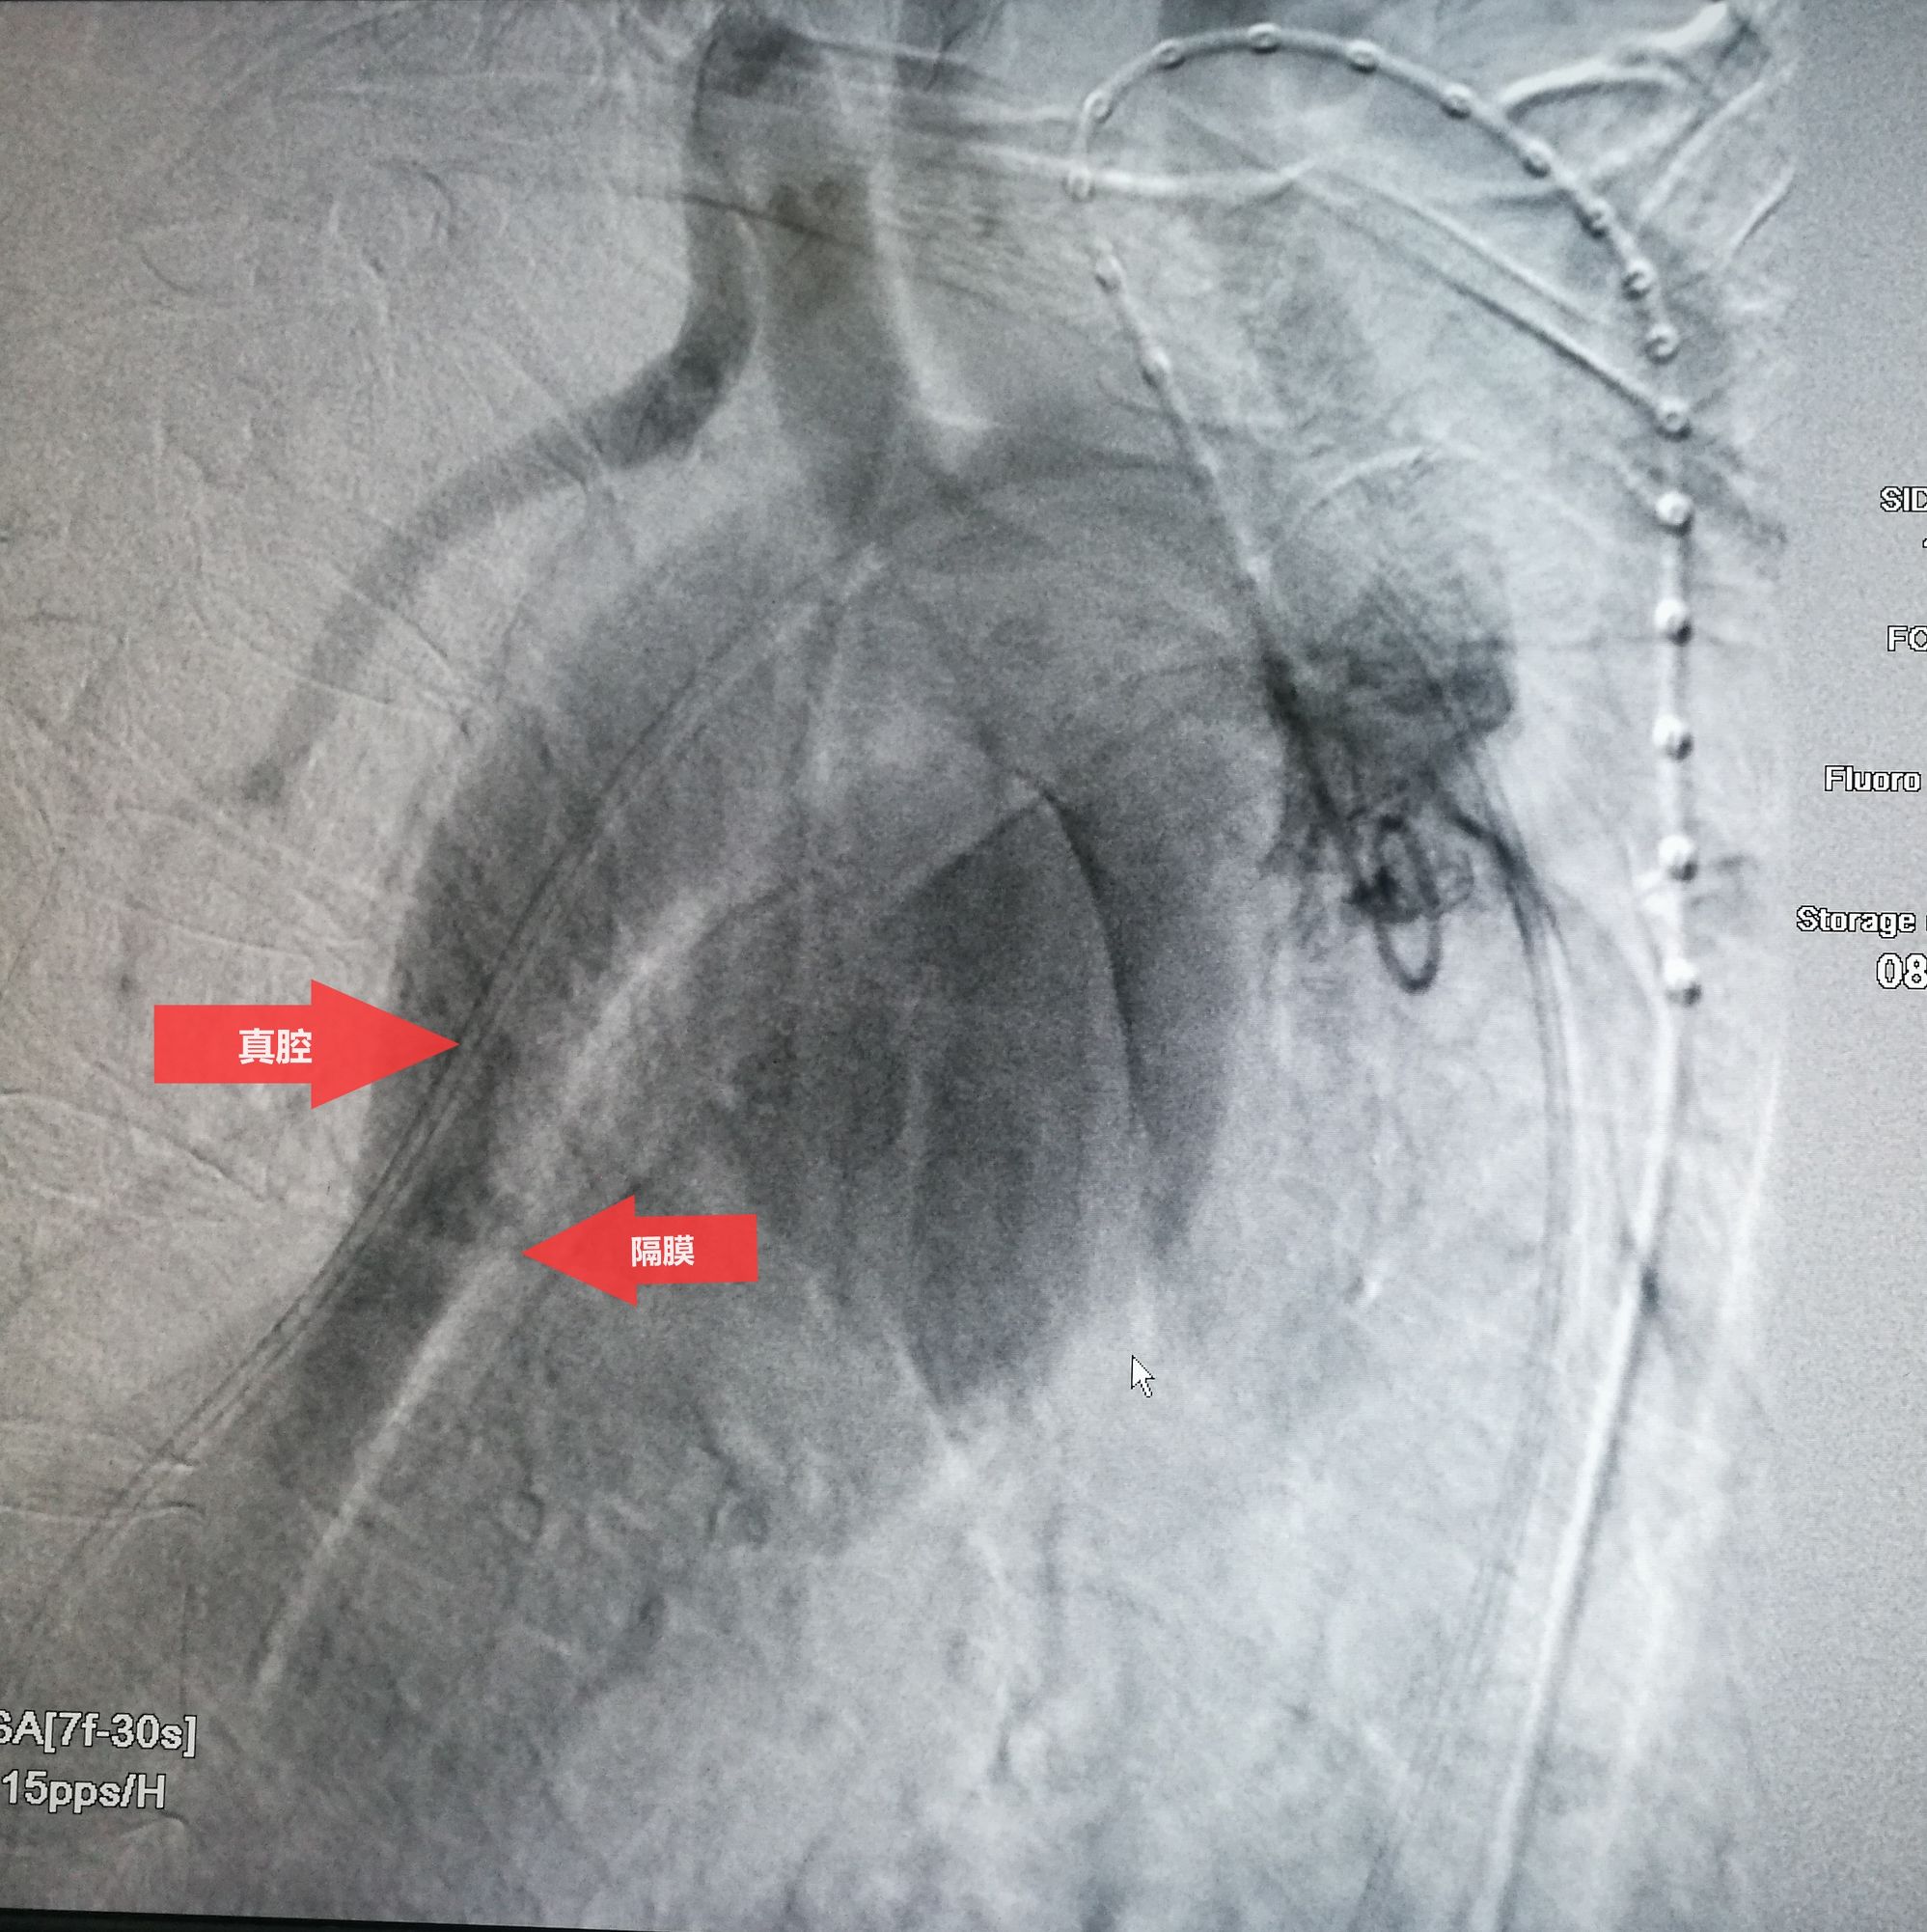

手术在局麻下进行,经右股动脉穿刺置管到升主,经左桡动脉穿刺植入金标猪尾导管,造影,为确认真假腔,加做右前斜位造影,确认股动脉导管在真腔内,测量后植入覆膜支架。由于扭曲严重(腹主,膈肌附近,弓降),支架最初并未贴服大湾侧,支架送过锁骨下动脉后适当回撤,请拉释放导丝,此时支架整体向大弯侧轻微移动,考虑应力已经得到缓解。完全释放支架,定位良好,封堵完全无内漏。

尽管有加硬导丝,但从二维影像上看,支架并未贴着大弯侧走行